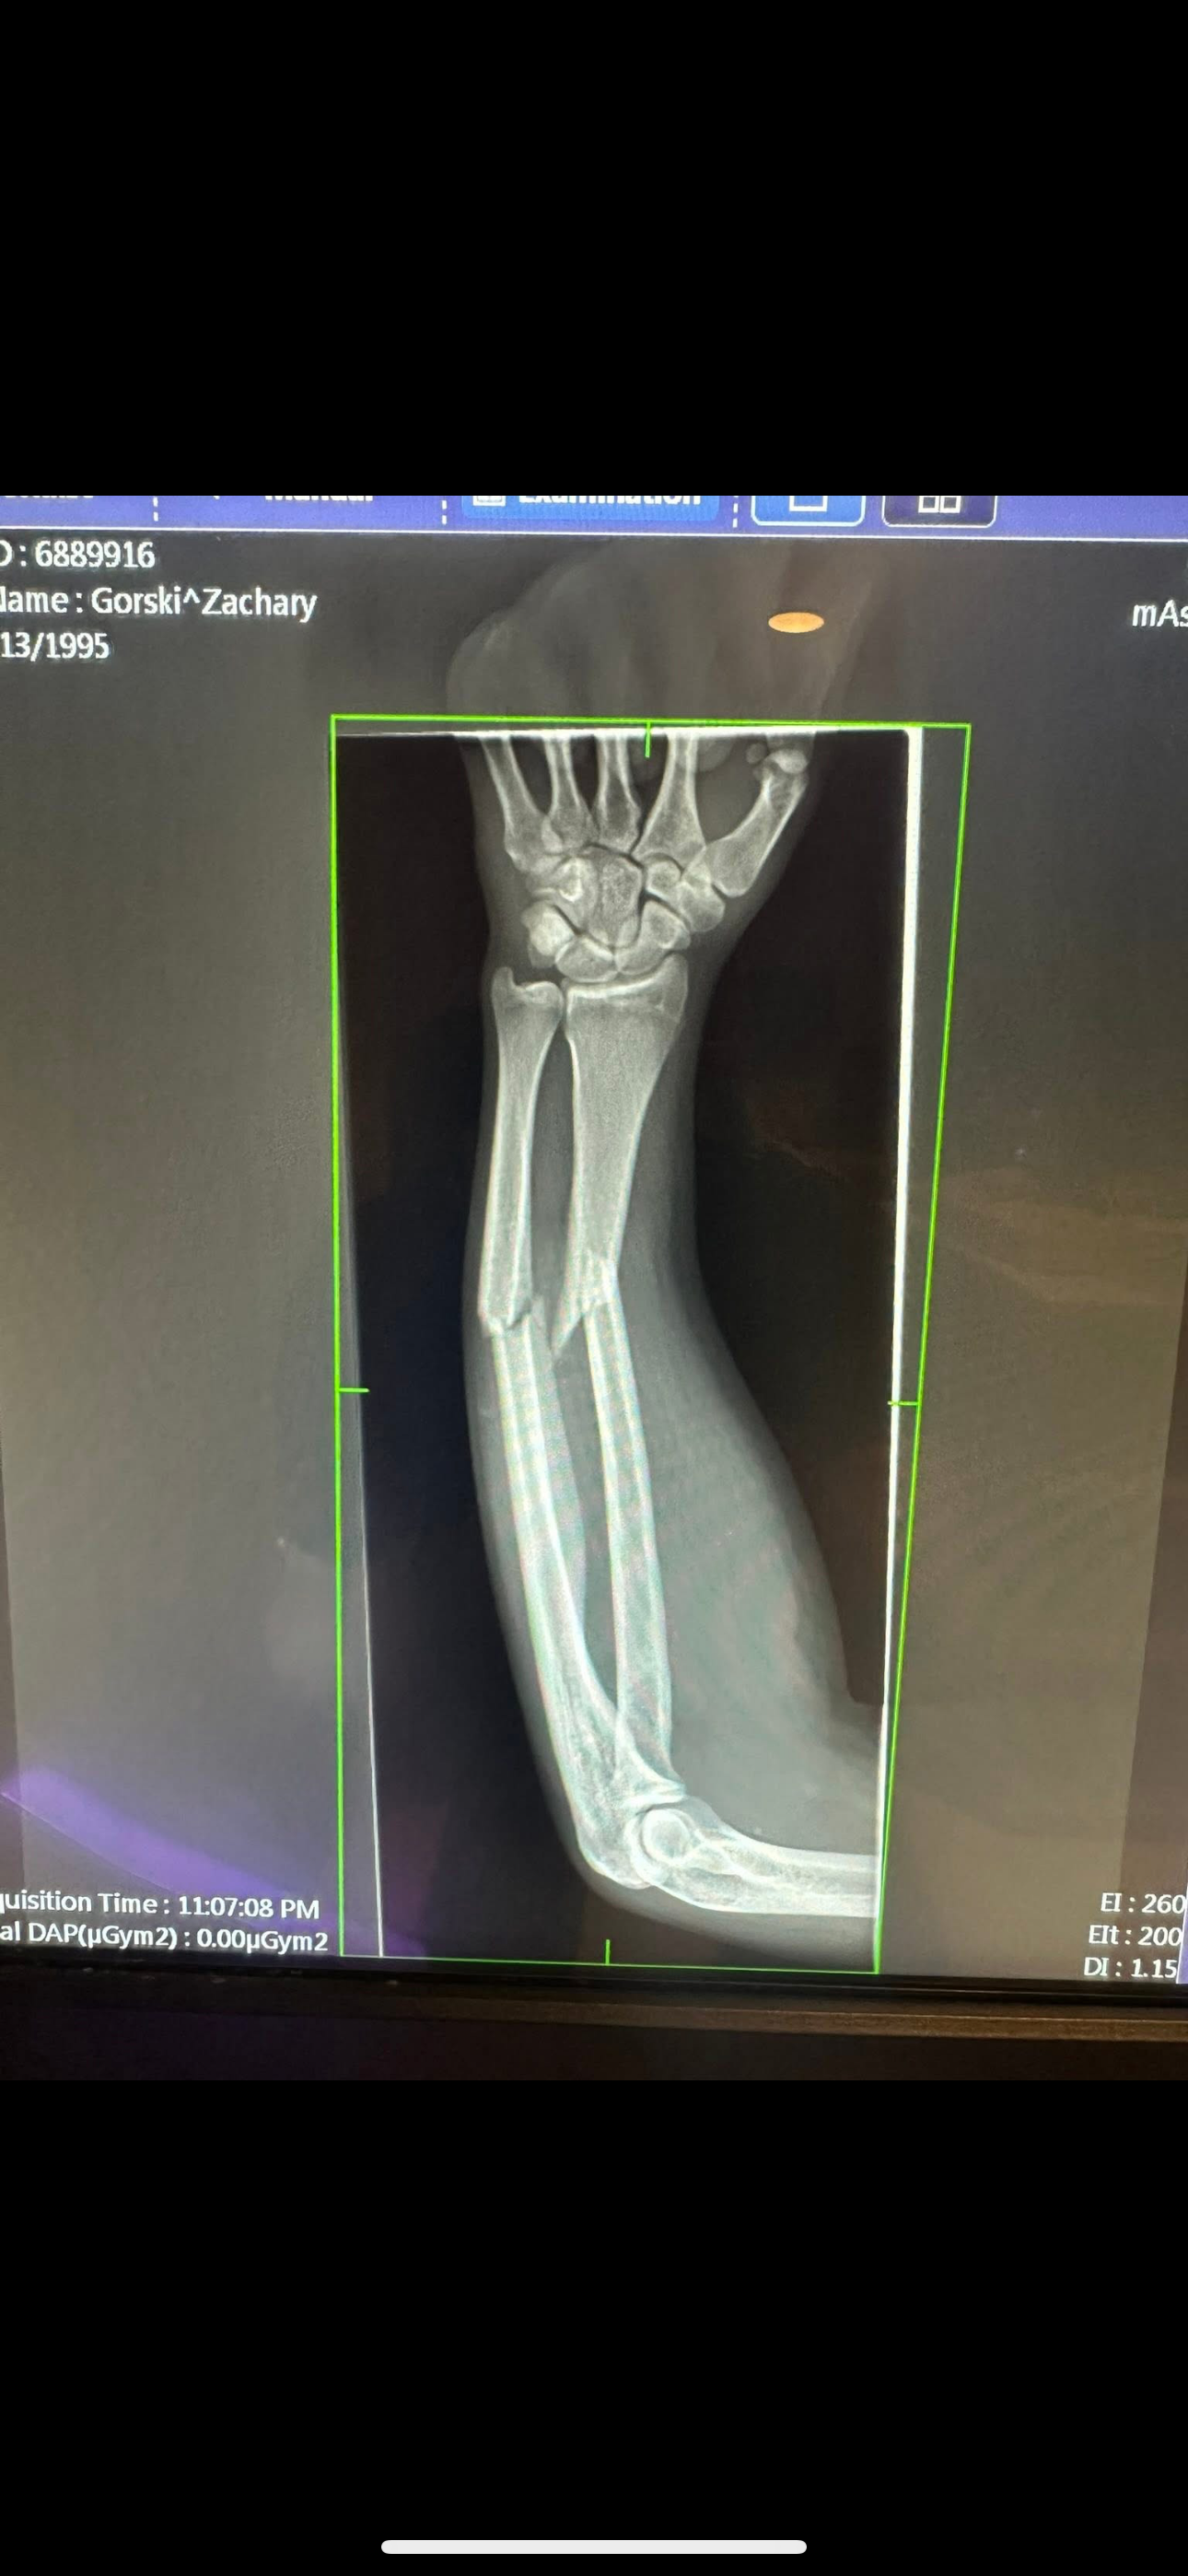

As most of you all know, my brother in law Zak Gorski was involved in a wreck during a micro sprint race this past weekend at Greenwood Valley Action Track, in Pennsylvania. Unfortunately, Zak was injured in this wreck. We are so lucky and thankful that he was able to walk away without any neck or back injuries; Zak was transported by ambulance to the hospital where he was told he suffered a pretty bad break to his left arm to which he is in need of surgery to repair. As of right now the surgery is scheduled for this Wednesday, the 20th.